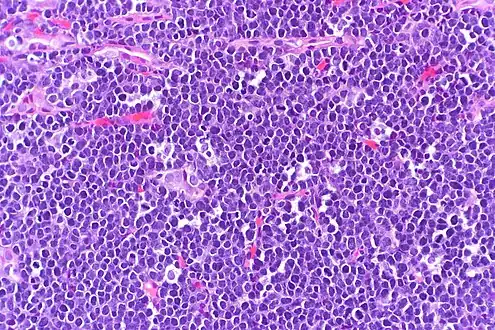

High-power view of Burkitt lymphoma with "starry sky" appearance. H&E stain.

The tumor consists of sheets of a monotonous (i.e., similar in size and morphology) population of medium-sized lymphoid cells with high proliferative and apoptotic activity. The "starry sky" appearance seen[21] under low power is due to scattered tingible body-laden macrophages (macrophages containing dead apoptotic tumor cells). The old descriptive term of "small non-cleaved cell" is misleading. The tumor cells are mostly medium in size (i.e., tumor nuclei size similar to that of histiocytes or endothelial cells). "Small non-cleaved cells" are compared to "large non-cleaved cells" of normal germinal center lymphocytes. Tumor cells possess small amounts of basophilic cytoplasm with three to four small nucleoli. The cellular outline usually appears squared off.